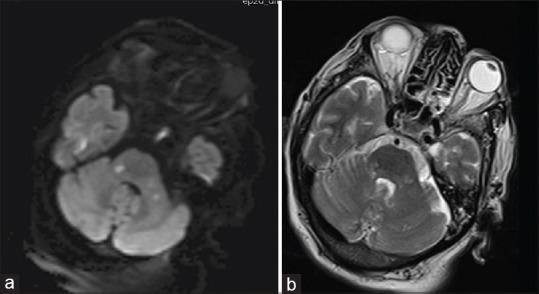

登革热脑炎——一组罕见病例

Dengue encephalitis - An unusual case series.

Dengue infection can take on many different forms, ranging from no symptoms to a mild fever, all the way to a severe condition known as dengue shock syndrome. Although the typical symptoms of dengue are well known, the virus can also cause rare neurological complications. Dengue encephalitis is a severe form of neuroinvasive dengue that can be fatal as the virus directly affects the central nervous system. This case series provides a comprehensive overview of dengue, its clinical spectrum, and the potential for severe neurological complications such as dengue encephalitis. It highlights the importance of considering dengue as a possible diagnosis in patients with encephalitis, particularly during a dengue epidemic.

摘要

登革热感染可呈现多种不同形式,从无症状到轻度发热,直至发展为一种名为登革热休克综合征的严重病症。尽管登革热的典型症状广为人知,但该病毒也可能引发罕见的神经系统并发症。登革热脑炎是神经侵袭性登革热的一种严重形式,由于病毒直接影响中枢神经系统,可能会导致死亡。本病例系列全面概述了登革热、其临床谱以及诸如登革热脑炎等严重神经系统并发症的可能性。它强调了在脑炎患者中,尤其是在登革热流行期间,将登革热视为一种可能诊断的重要性。

A rare case of dengue encephalopathy complicating a term pregnancy.一例罕见的登革热脑病合并足月妊娠病例。

BMC Res Notes. 2017 Feb 2;10(1):79. doi: 10.1186/s13104-017-2391-5.